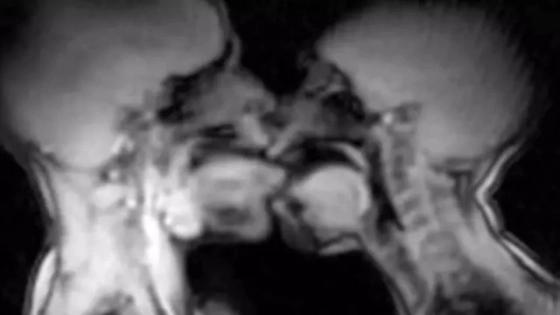

Çfarë zbuluan imazhet e rezonancës magnetike

Pamjet e MRI-së treguan se organi mashkullor nuk qëndron i drejtë gjatë marrëdhënies intime, por përkulet në mënyrë që të përshtatet me formën e trupit femëror. Ky zbulim rrëzoi teori të vjetra anatomike, përfshirë edhe disa ide të atribuuara Leonardo da Vinçit.

Në periudhën 1991–1999 u regjistruan gjithsej 13 raste marrëdhëniesh intime brenda MRI-së, me pjesëmarrjen e tetë çifteve dhe tre grave. Në shumicën e rasteve, meshkujt u detyruan të përdornin Viagra për shkak të kushteve jashtëzakonisht të vështira të eksperimentit.